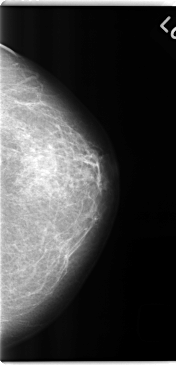

C_0251_1.LEFT_CC

LEFT_CC LINES 4744 PIXELS_PER_LINE 2288 BITS_PER_PIXEL 12 RESOLUTION 50 NON_OVERLAY